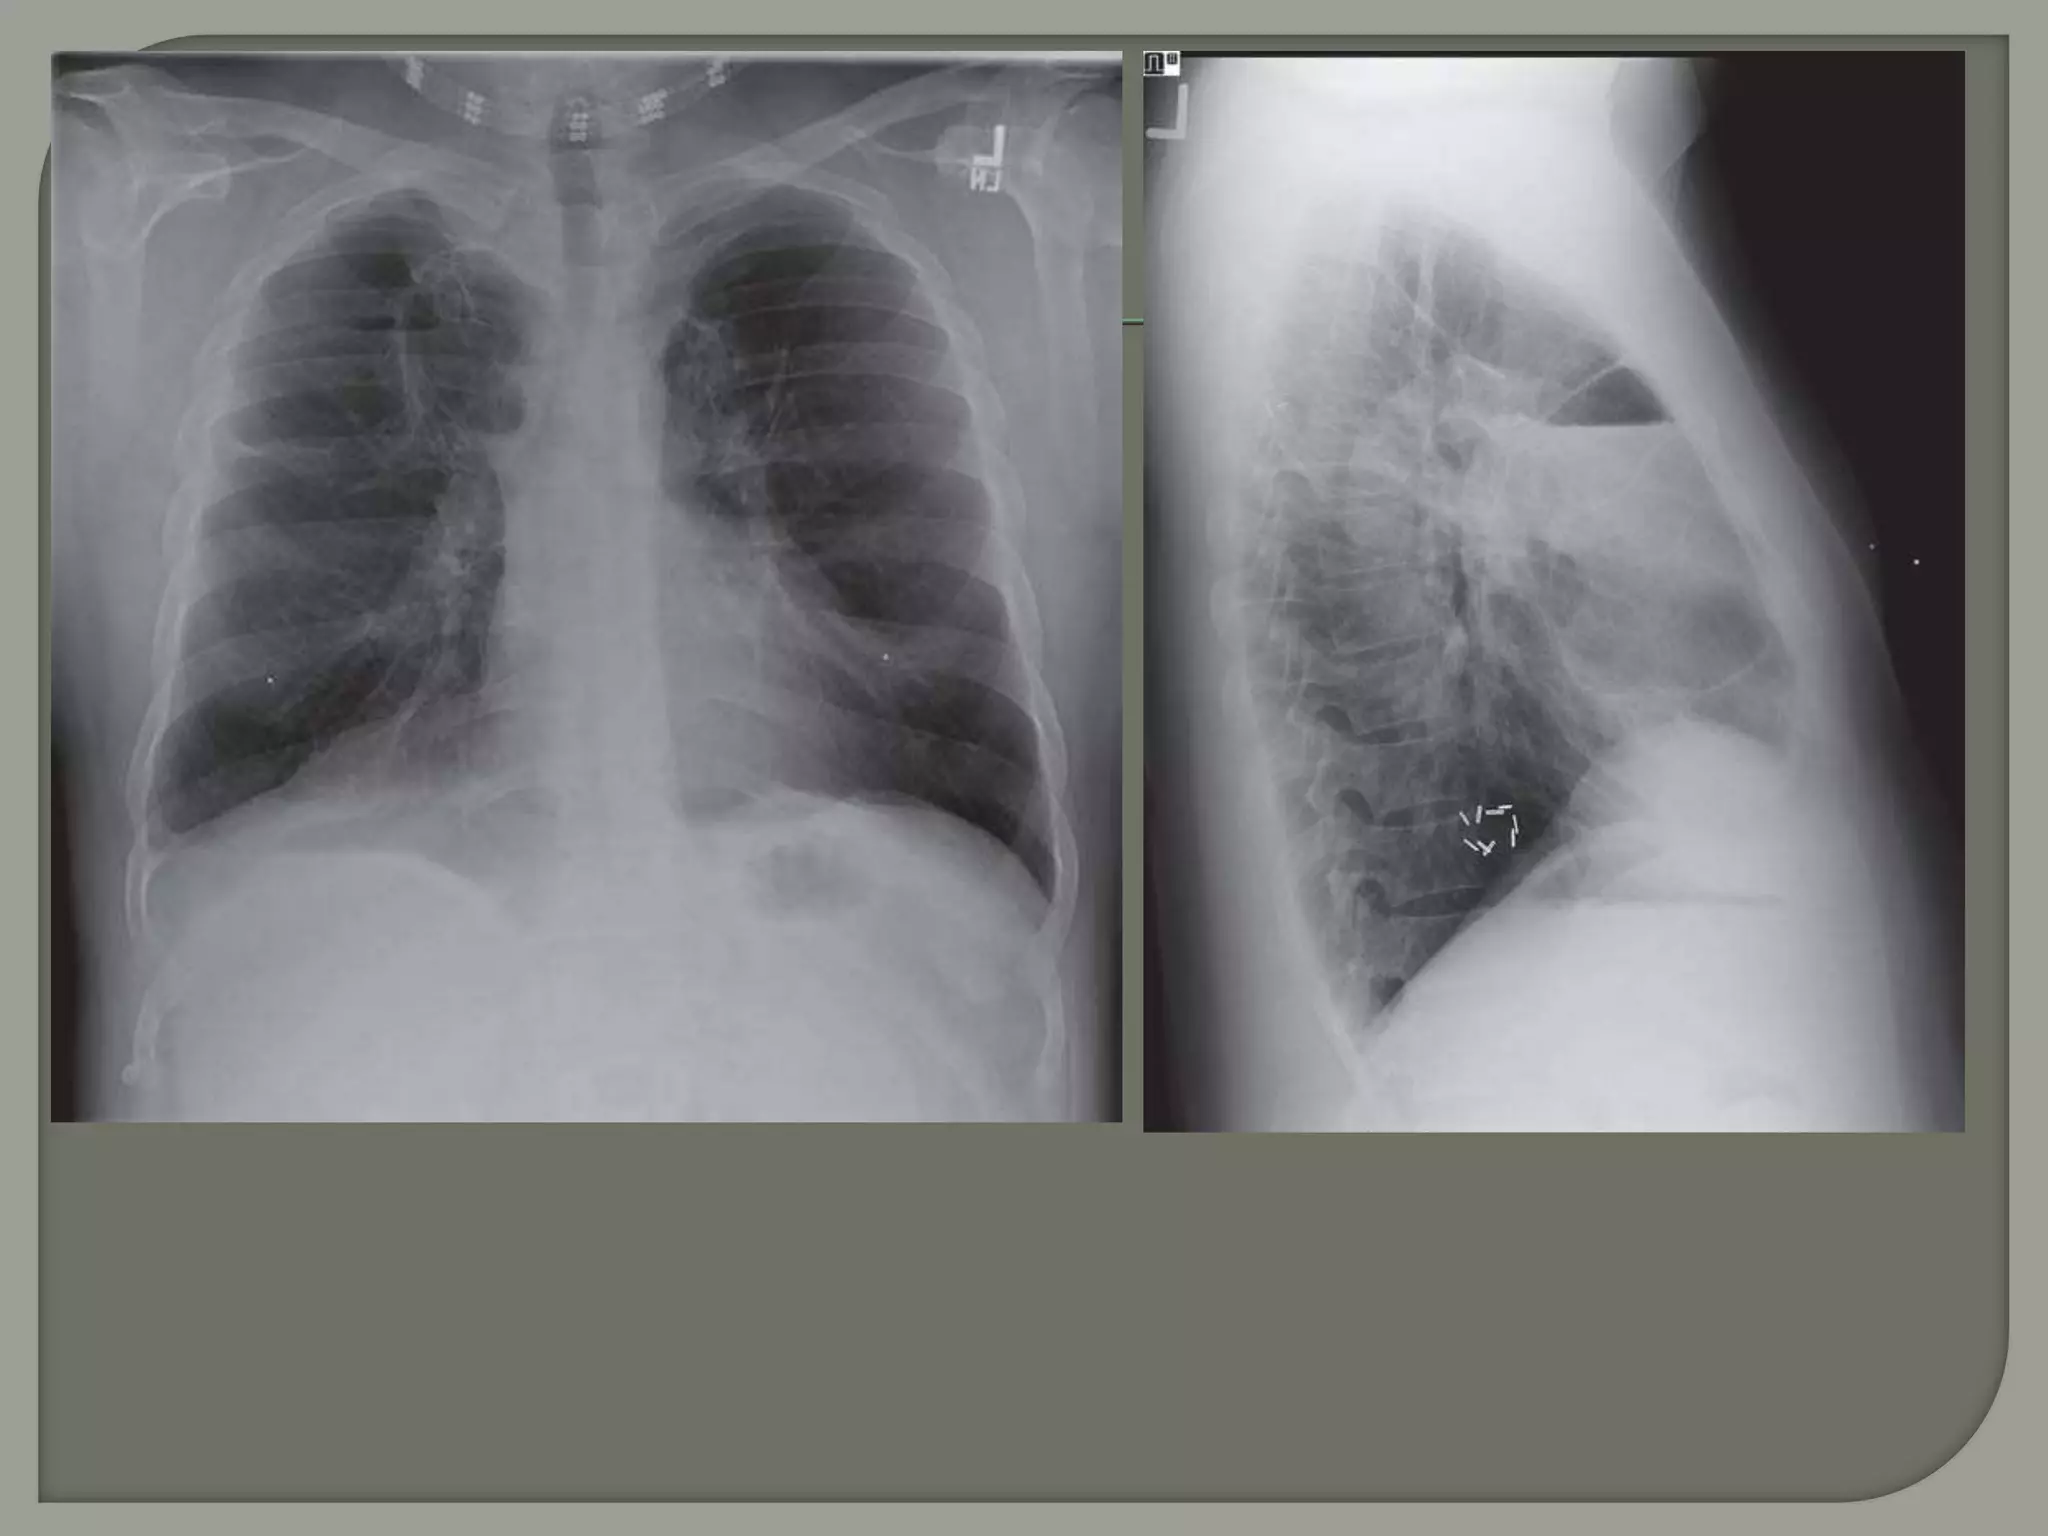

 CXR

 CT

“hairline

shadows”